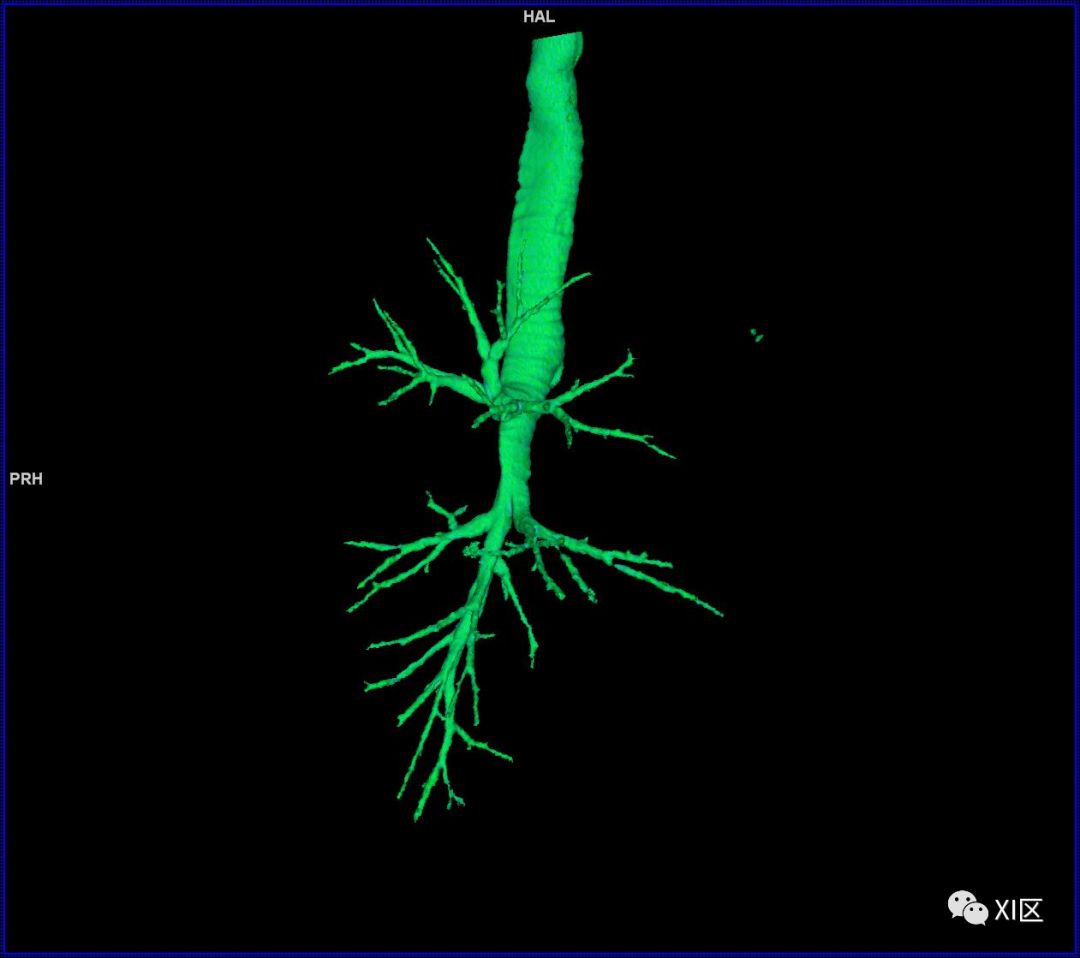

气管树

气管树与左右肺的关系

气管支气管形如树状,因此也称气管支气管树。